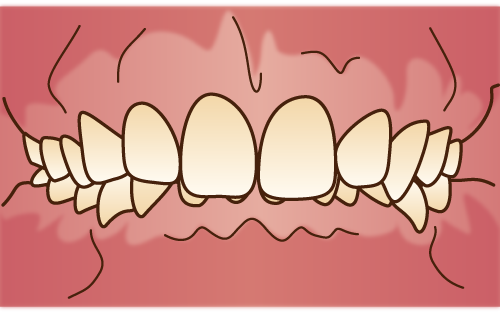

開咬

不正咬合(開咬)

○奥歯で咬んでも前歯が咬み合わずに上下の歯の間が開いている状態。

○指しゃぶり・吸唇癖・舌癖などの口腔習癖や、おしゃぶりの常用による。○口呼吸(鼻づまり)による。 |